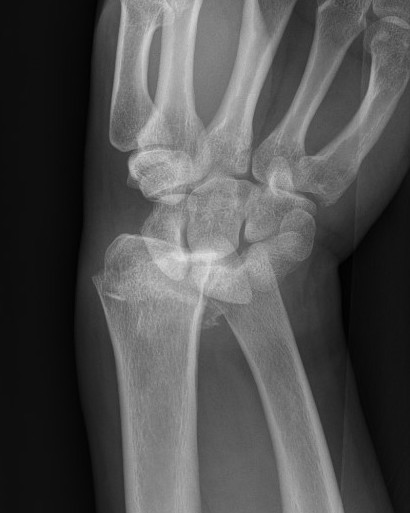

Dorsal radiocarpal dislocation with dorsal rim fracture

Dorsal radiocarpal dislocation with radial styloid fracture